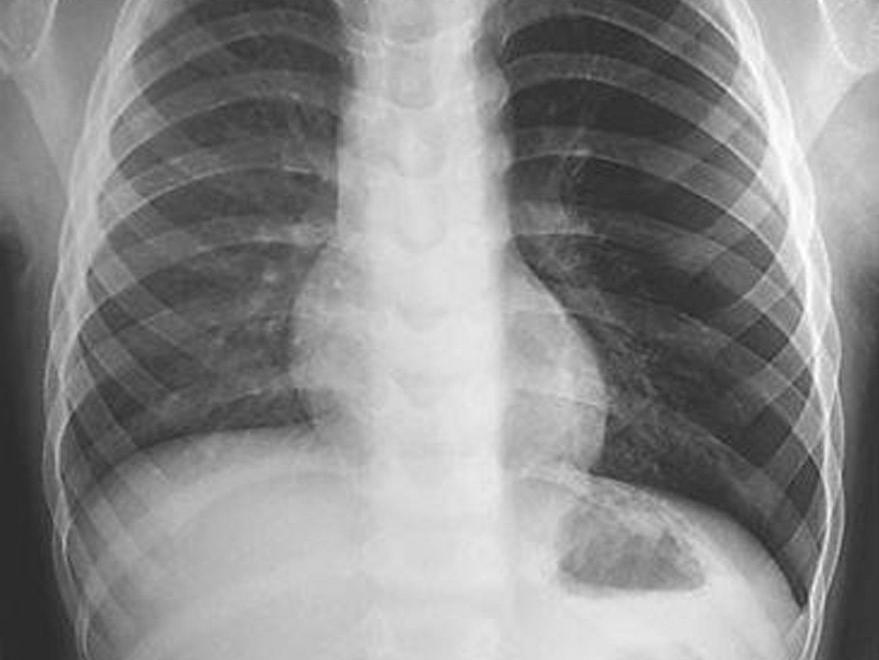

Çocuğun vücudunun sol tarafındaki şişlik röntgen sonuçlarında rahatlıkla görülüyor. Çocuğun vücudunun sol tarafındaki şişlik röntgen sonuçlarında rahatlıkla görülüyor.

Durumdan şüphelenen ve endişelenen aile, doktora götürdüğünde ise bir şok daha yaşadı. Çocuğun röntgeni çekilirken, doktorlar durumu inceledi ve sol göğsündeki ciğerlerde bir şişlik olduğunu fark etti. İncelemeyi detaylandıran yetkililer çocuğun bronşunda bir düdük bulunduğunu tespit etti.